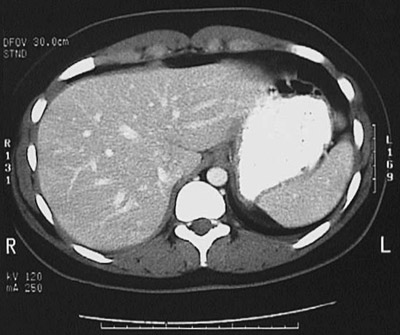

[T11] This is a normal abdominal CT scan with contrast demonstrating the upper abdomen with the stomach and spleen and diaphragm and liver and vertebral body and spinal canal and aorta .